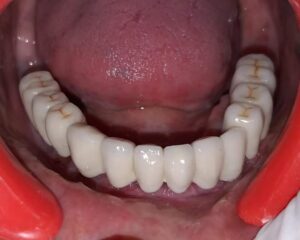

- બધા દાંત કે બત્રીસી ને ઇમ્પ્લાન્ટ થી ફિક્સ કરી સકે છે.

અમારી હોસ્પિટલ માં કરેલ ડેન્ટલ ઇમ્પ્લાન્ટ ના ફોટો

જો તમારા બધા દાંત કાઢી નાખેલ છે, તો ઇમ્પ્લાન્ટ સપોર્ટેડ ફુલ બ્રિજ અથવા સંપૂર્ણ ચોખઠાને ઇંપ્લાંટ થી ફિક્સ કરી શકાય છે .